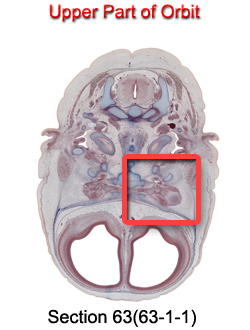

Upper Part of Orbit

Carnegie Embryo #9226

63-01-01